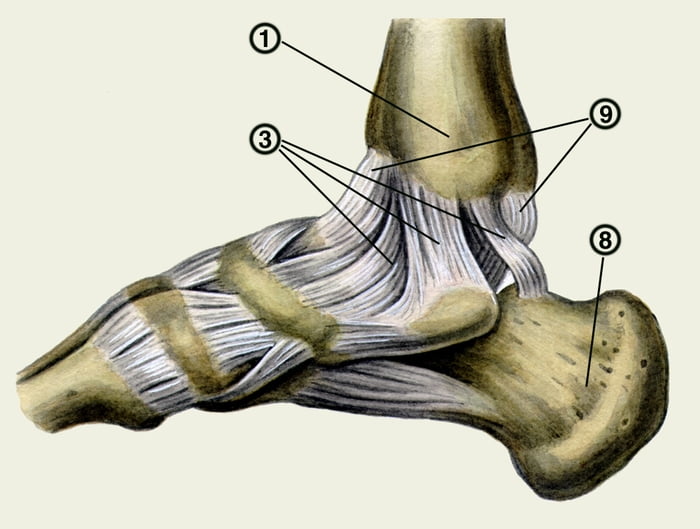

Анатомия голеностопа: Сухожилия и их строение